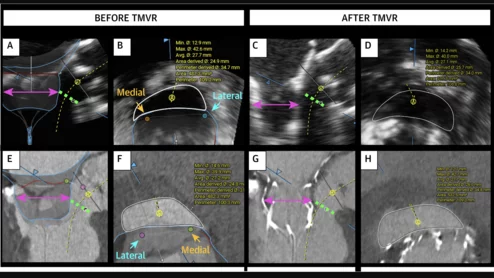

Echocardiography vs CT for Prediction of Newly Created LVOT Area during TMVR

LVOT obstruction after TMVR remains a significant concern among structural heart cardiologists. Predicting the risk of LVOT obstruction typically requires CT, which comes with certain disadvantages compared to other imaging options.